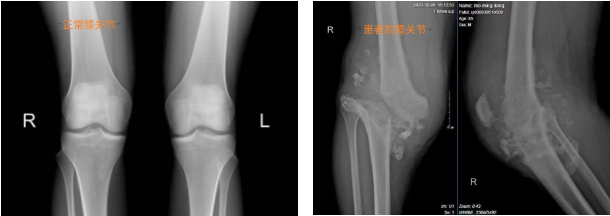

患者术前膝关节图片

膝关节X线图片对比